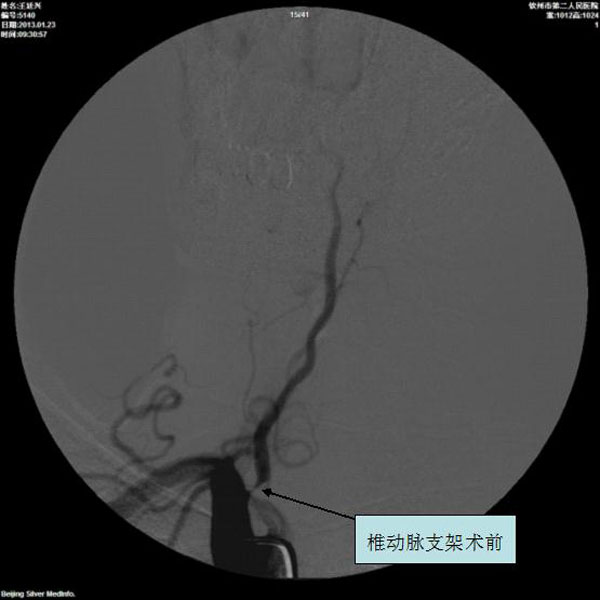

椎动脉支架术前

椎动脉支架术后